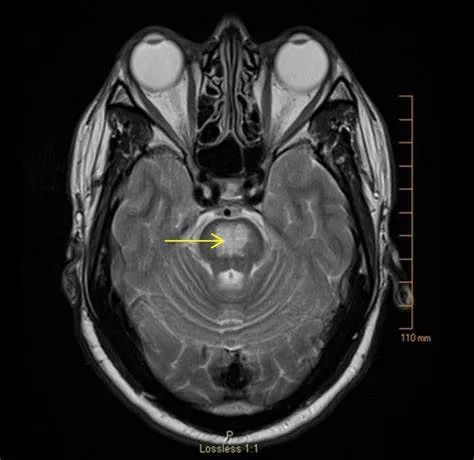

(2)CPM,病灶多位于桥脑基底部而桥脑腹侧不受累,病灶形状多种多样,可为条片状(位于中脑基底部中线,如本例)、斑片状、圆形或卵圆状、「三叉戟」或「猪鼻」样,T1WI 呈低信号,T2WI 及 FLAIR 呈高信号,病灶边界清晰,部分患者出现 DWI 高信号,有利于疾病的早期发现,出现强化提示血脑屏障破坏。

圆形病灶,位于桥脑基底部,桥脑腹侧及被盖未受累